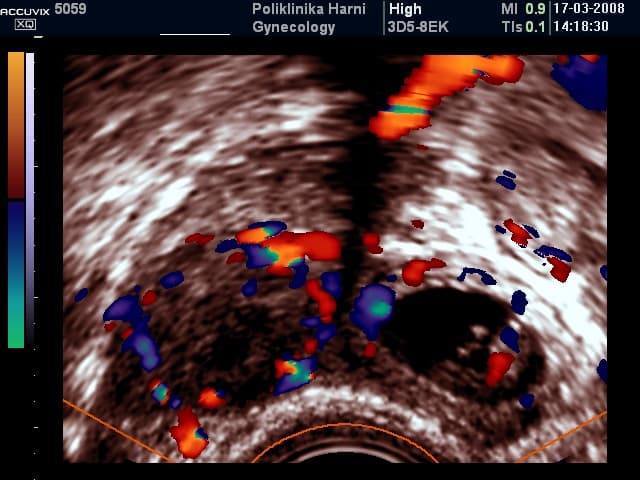

Kod vaginalnog pregleda u početnim stadijima ne mora se nalaziti nikakvih abnormalnosti, dok se kod uznapredovalih stadija ili krvarenja u trbuh palpira se adneksalna masa uz izrazitu bolnost pri pomicanju vrata maternice. Sigurni ultrazvučni znak ektopične trudnoće je nalaz vitalnog embrija izvan maternice. Vjerojatni znaci / trijas ultrazvučnih biljega za ektopiočnu trudnoću su nedostatak ultrazvučnih znakova trudnoće u maternici, adneksalni tumor i prisutnost tekućine u trbuhu. Sumnjivi ultrazvučni nalaz je već i nedostatak nalaza embrija u maternici kod izostanka menstruacije.